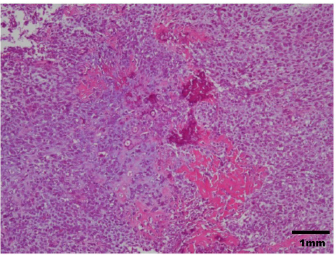

AbstractBackground: There are few detailed reports on implant-associated sarcoma in dogs; however, loose implants, metal type, and infection have not been shown as specific risk factors for this condition. Case Description: A 14-year-old spayed female Labrador retriever was referred to our hospital with a main complaint of chronic right hind lameness after previous tibial fracture repair. On radiographs, rupture of the bone plate and screws with swelling of the surrounding soft tissue was observed, and osteosarcoma (OSA) was diagnosed after histopathological examinations. During amputation surgery, a plastic band was found associated with the implant. Conclusion: Veterinary surgeons should be aware of implant-associated OSA and refrain from using non-medical materials in the implants. Furthermore, they should recommend the removal of orthopedic implants after fracture repair. Keywords: Dogs, Fracture, Implant, Osteosarcoma, Repair. IntroductionOsteosarcoma (OSA) is a highly aggressive mesenchymal tumor that comprises at least 85% of canine bone tumors (Egenvall et al., 2007) and tends to occur in larger individuals, and the most common site in dogs is in the appendicular skeleton near metaphyses (Morello et al., 2011). Several studies have suggested that OSAs result from abnormalities in osteoblast differentiation, as mesenchymal stem cells differentiate through osteoprogenitor and osteoblast phases before becoming mature osteocytes (Tang et al., 2008). Osteoblastic features are common in OSA, suggesting that early disruption of osteogenic differentiation may occur during sarcoma development (Tang et al., 2008). Furthermore, this process is sometimes initiated by the presence of orthopedic implants (Murphy et al., 1997; Rose et al., 2005). Loose implants, metal type, and infection have not been shown to be specific risk factors of implant-associated sarcoma (Sinibaldi et al., 1976; Kenecht et al., 1978; MacDonald et al., 2012). There have been a few reports on implant-associated sarcoma in dogs, albeit with minimal information (Burton et al., 2015; Arthur et al., 2016). Our case describes canine implant-associated OSA at the site of a previous fracture, repaired with bone plate and screws and an unknown plastic band. Case DetailsA 14-year-old spayed female Labrador retriever weighing 21.3 kg was referred to our hospital with a main complaint of chronic right-hind lameness. This patient had undergone surgery for right tibial fracture repair with implantation of bone plate and screws at a referral hospital 12 years ago. The patient showed no appetite, was not drinking, and was lethargic, with a body condition score of 1/5. The patient was unable to stand up on her own, her right hind limb was mostly weak, and she was unable to move independently using her left side. The patient’s state of consciousness was normal. On physical examination, her vital signs were normal (temperature: 38.1°C, pulse 104 beats/minutes with no heart murmur, respiratory rate with normal lung sounds: 32 beats/minutes). The mucous membrane showed a pale color because of severe anemia (packed cell volume 20.4%). In addition, the capillary refill time was delayed by <3 seconds, suggesting severe dehydration. The patient showed swelling and was warm to the touch from the right tibia to the femur, with a swollen right popliteal lymph node, which presented with a ruptured mass lesion approximately 7 × 10 cm in size. The thoracic radiograph was normal (Fig. 1). However, the right hind limb radiograph showed an osteolytic lesion accompanying the ruptured implant and loosening of the plate and screws, with surrounding soft tissue swelling (Fig. 2). Fine needle aspiration from this site suggested OSA (data not shown). Although we could not perform angiographic computed tomography because of the owner’s dissent, we performed amputation from the hip joint on the same day. Gross morphology showed severe inflammation surrounding soft tissues, the rupture of the stainless-steel bone plate, and we noted a non-medical band at the right tibia (Fig. 3). The patient was formally diagnosed with OSA after histopathological examinations (Fig. 4). After 24 hours hospitalization, we administered ampicillin potassium (20 mg/kg, BID) intravenously and prednisolone (0.5 mg/kg, SID) subcutaneously for postoperative care. Also, 24 hours continuous rate infusion of fentanyl (5 μg/kg/minutes) in lactated Ringer’s solution was used for analgesia. The patient was discharged to the owner the day after surgery for home care. The owner refused postoperative radiation therapy and chemotherapy. Unfortunately, this patient died 1 month after amputation.

Fig. 4. Histopathological diagnosis was OSA. Although the interaction between vinyl chloride and OSA has not been reported in dogs, various chemicals (fluoride, beryllium, and vinyl chloride), exposure to radiation, and viruses have been identified as factors, inducing OSA, in humans (Operskalski et al., 1987). The patient in this case report did not have radiation therapy, no medical record of virus infection, or family history of OSA. Hence, we concluded that the vinyl chloride bands might be associated with the development of OSA. In summary, veterinary surgeons should be able to recognize implant-associated OSA and should be discouraged from using non-medical materials in implants. Furthermore, we recommend the removal of orthopedic implants after fracture repair. Conflict of interestThe authors declare that there is no conflict of interest. Authors’ contributionsMitsuhiro Isaka, Daiki Kokubo, and Toshikazu Sakai conceived and performed the procedure, drafted and revised the manuscript, and approved the final version. ReferencesArthur, E.G., Arthur, G.L., Keeler, M.R. and Bryan, J.N. 2016. Risk of osteosarcoma in dogs after open fracture fixation. Vet. Surg. 45, 30–35. Burton, A.G., Johnson, E.G., Vernau, W. and Murphy, B.G. 2015. Implant-associated neoplasia in dogs:16 cases (1983-2013). J. Am. Vet. Med. Assoc. 247, 778–785. Egenvall, A., Nodtvedt, A. and von Euler, H. 2007. Bone tumors in a population of 400000 insured Swedish dogs up to 10 y of age: incidence and survival. Can. J. Vet. Res. 71, 292–299. Kenecht, C.D. and Priester, W.A. 1978. Osteosarcoma in dogs: a study of previous trauma, fracture and fracture fixations. J. Am. Anim. Hosp. Assoc. 14, 82–84. Kirkpatrick, C.J., Alves, A. and Köhler, H., Kriegsmann, J., Bittinger, F., Otto, M., Williams, D.F. and Eloy. 2000. Biomaterial-induced sarcoma: a novel model to study preneoplastic change. Am. J. Pathol. 156, 1455–1467. MacDonald, D.J., Enneking, W.F. and Sundaram, M. 2002. Metal-associated angiosarcoma of bone: report of two cases and review of the literature. Clin. Orthop. Relat. Res. 396, 206–214. Morello, E., Martano, M. and Buracco, P. 2011. Biology, diagnosis and treatment of canine appendicular osteosarcoma: similarities and differences with human osteosarcoma. Vet. J. 89, 268–277. Murphy, S.T., Parker, R.B. and Woodard, J.C. 1997. Osteosarcoma following total hip arthroplasty in a dog. J. Small. Anim. Pract. 38, 263–267. Operskalski, E.A., Martin, S.P., Henderson, B. and Vicsher, B, R. 1987. A case control study of osteosarcoma. Am. J. Epidemiol. 126, 118–119. Rose, B.W., Novo, R.E. and Olson, E.J. 2005. Osteosarcoma at the site of a triple pelvic osteotomy in a dog. J. Am. Anim. Hosp. Assoc. 41, 327–331. Sinibaldi, K., Rosen, H. and Liu, S.K. and DeAngelis, M. 1976. Tumor associated with metallic implants in animals. Clin. Orthop. 118, 257–266. Tang, N., Song, W.X. and Luo, J., Haydon, R.C. and He, TC. 2008. Osteosarcoma development and stem cell differentiation. Clin. Orthop. Relap. Res. 466, 2114–2130. Visuri, T., Pulkkinen, P. and Paavolainen P. 2006. Malignant tumors at the site of total hip prosthesis. Analytic review of 46 cases. J. Arthroplasty. 21, 311–323. | ||